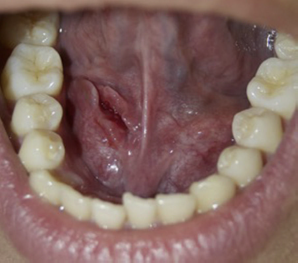

En el examen extraoral presentaba simetría facial, sin adenopatías palpables ni masa cervical evidente. Al realizar el examen intraoral se manifiesta una lesión ovoide de 7 × 4 cm en la región sublingual derecha, unilateral, que no cruza la línea media; fluctuante, de color translúcido edematoso e indoloro, que eleva y desvía la lengua al lado contralateral (fig. 1). Se realizó una hipótesis diagnóstica de ránula intraoral, la cual se complementó mediante examen imagenológico tomográfico (TC) con medio de contraste para confirmar la presencia de una lesión quística unilocular, ovalada, de baja densidad, confinada al espacio sublingual, además de evaluar su extensión anatómica confirmando su ubicación intraoral/superficial (fig. 2).

Se decide su tratamiento quirúrgico conservador siguiendo el protocolo de la técnica de marsupialización modificada. Bajo anestesia local (articaína 4%) con bloqueo directo del nervio lingual ipsilateral, se realizó la transfixión con hilo de sutura no absorbible seda 4,0 (Silk®) en la superficie de la mucosa del piso de la boca con los bordes de la lesión. Después de delimitar el campo se realizó una incisión aguda de la mucosa y cápsula a lo largo de su eje mayor (pared superior de la ránula). Con la incisión hecha y la retirada de la pieza para estudio histopatológico, se vació el contenido mucoso, permitiendo la resección de la parte superficial del quiste. Se introdujo con un elemento de contención impregnado con antiséptico intralesional (gasa impregnada en Furacín®) para que no colapse la cavidad quística, la cual se sutura en la periferia para impedir su desalojo con los movimientos (fig. 3). Se indicó irrigar la cavidad con clorhexidina al 0,12% 10 ml 2 veces al día por 10 días. Como tratamiento farmacológico se le indicó amoxicilina comprimidos 500 mg cada 8 h por 7 días, e ibuprofeno 600 mg cada 8 h por 3 días. Para su control y seguimiento se citó a los 3, 7 y 10 días (fig. 4). Al décimo día se eliminó el elemento de contención (fig. 5). Se realizó un seguimiento clínico por 12 meses, sin observarse signos de recidiva de la lesión (fig. 6).